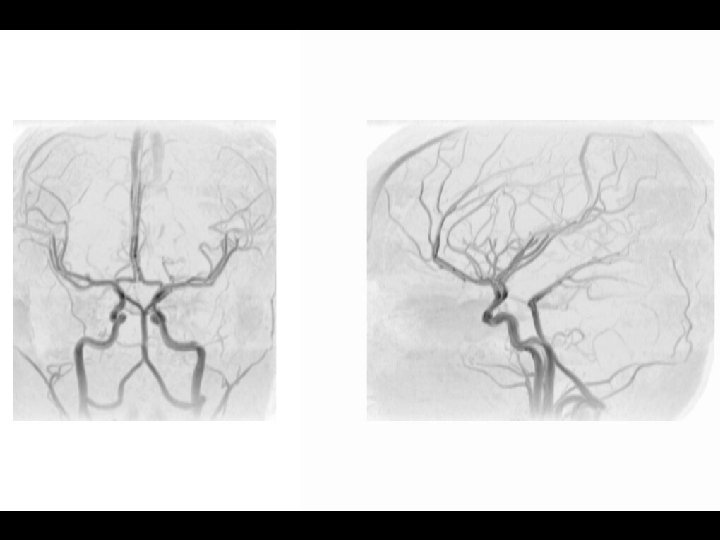

Arterial Blood Supply Arterial Blood Supply

Anterior circulation Internal carotid arteries Posterior circulation Vertebral arteries Anterior circulation Internal carotid arteries Posterior circulation Vertebral arteries